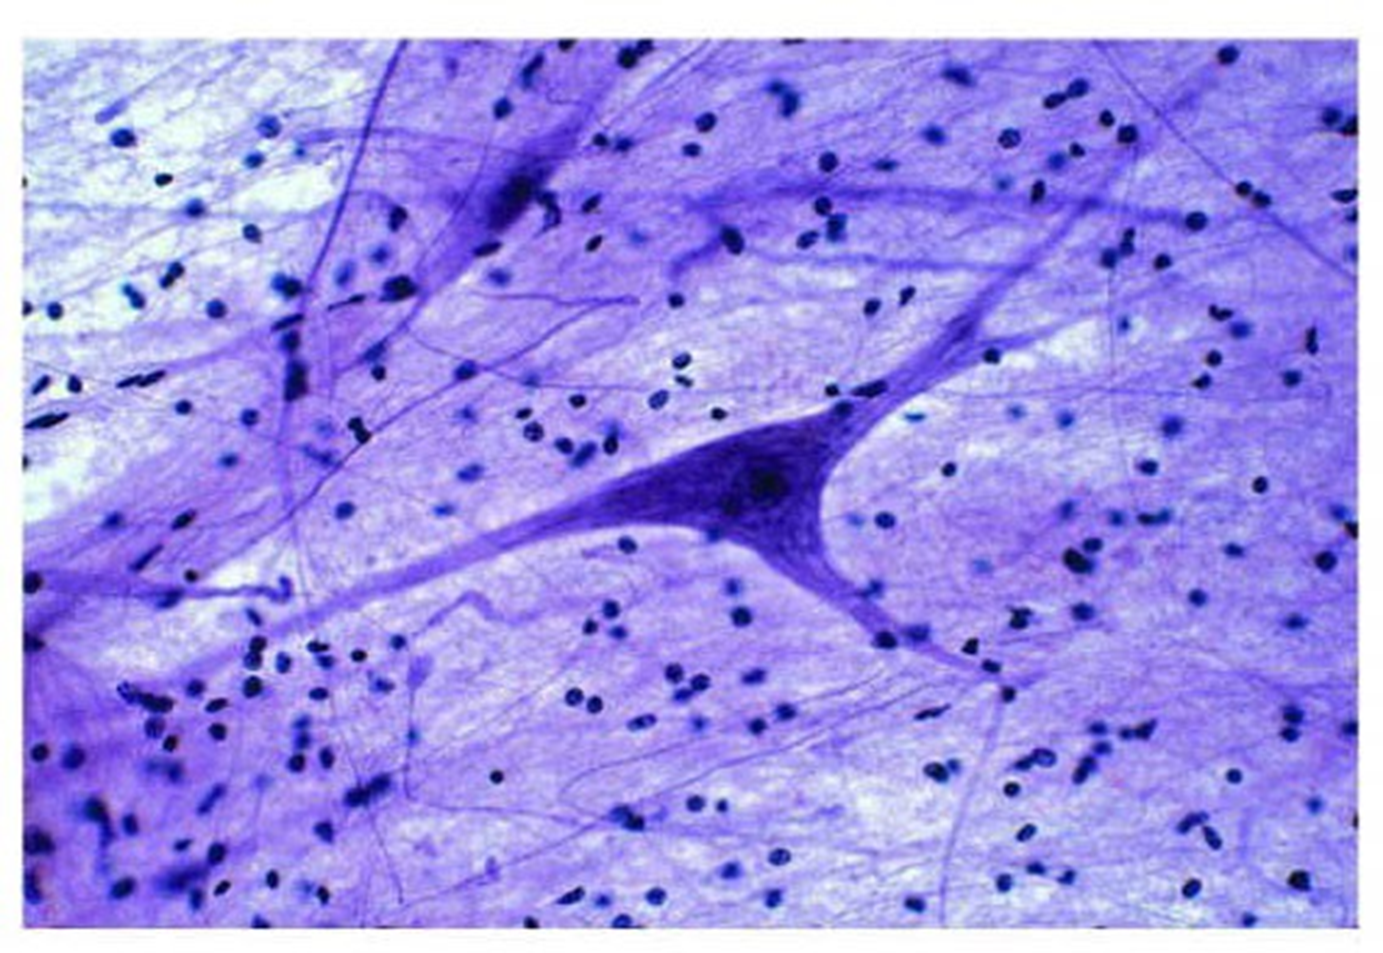

nervous tissue

-characterized by presence of neurons and neuroglia -neurons are the functional cells of ….

23